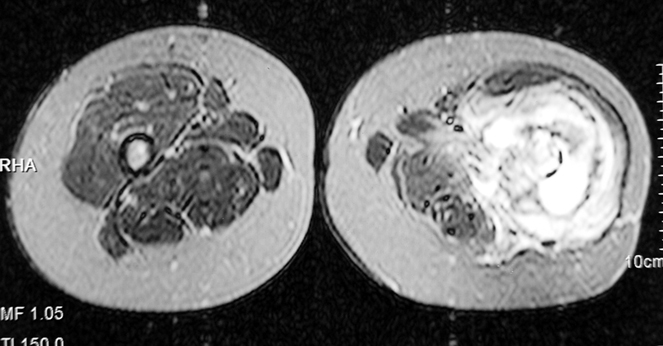

Chronic osteomyelitis leads to necrosis of bone and soft tissues. Dead bone is a nidus which hosts pathogenous microorganisms. Defence mechanisms of the host is usually not in optimum condition to deal with microorganisms. Antibiotics can’t reach the infection site because blood flow is disrupted. For these reasons, dead bone has to be completely removed by radical debridement.

Appropriate radical debridement necessitates excision of all necrotic bone and soft tissues, and frequently causes instability at the involved extremity. The remaining bone and soft tissue defect has to be fixed and reconstructed. The distraction osteogenesis method of Ilizarov is used successfully for achievement of union, correction of the deformity, elimination of limb length inequality and reconstruction of segmental bone defects.

The duration of external fixation (external fixation index) depends on the amount of distraction required, and the extremity is prone to complications during this period. After the distraction phase is completed, the external fixator remains in place during the consolidation phase, which lasts twice as long as the distraction phase; but this period is hardly tolerated. If the external fixator is removed before sufficient consolidation is achieved, fractures, deformity and shortness will be the result. In our department, ‘lenghthening over nail’ method is used in order to decrease the external fixation index and increase patient comfort and activity level. In this method, the intramedullary nail is statically locked after the completion of the distraction phase, and external fixator is removed. The extremity is stabilized by the intramedullary nail during consolidation phase. In this way, complications due to long external fixation index or early removal of the external fixator are avoided.